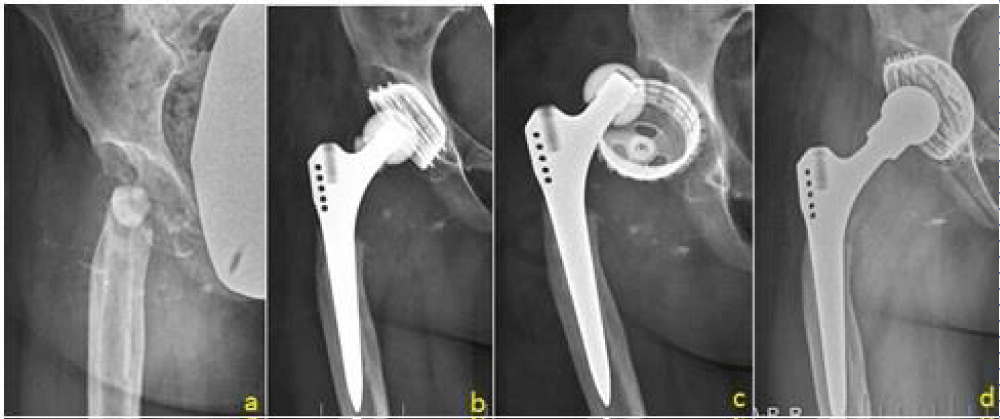

Among the total study population, 10.4% had indication of necrosis of the femoral head. These cases consisted of such conditions as chondrolysis of the hip joint, following coxitis (including the stages after tuberculosis coxitis), or necrosis resulting from radiation therapy or in relation to hemophilia (Figure 2).

Figure 2: A patient requiring hip revision surgery following septic coxitis with necrosis of the head of the femur. The patient underwent THR. (a) 3-months post-operative. (b) 6-months post-operative. (c) Aseptic loosening of the cup detected at 9 months follow-up. (d) Re-implantation with larger cup.